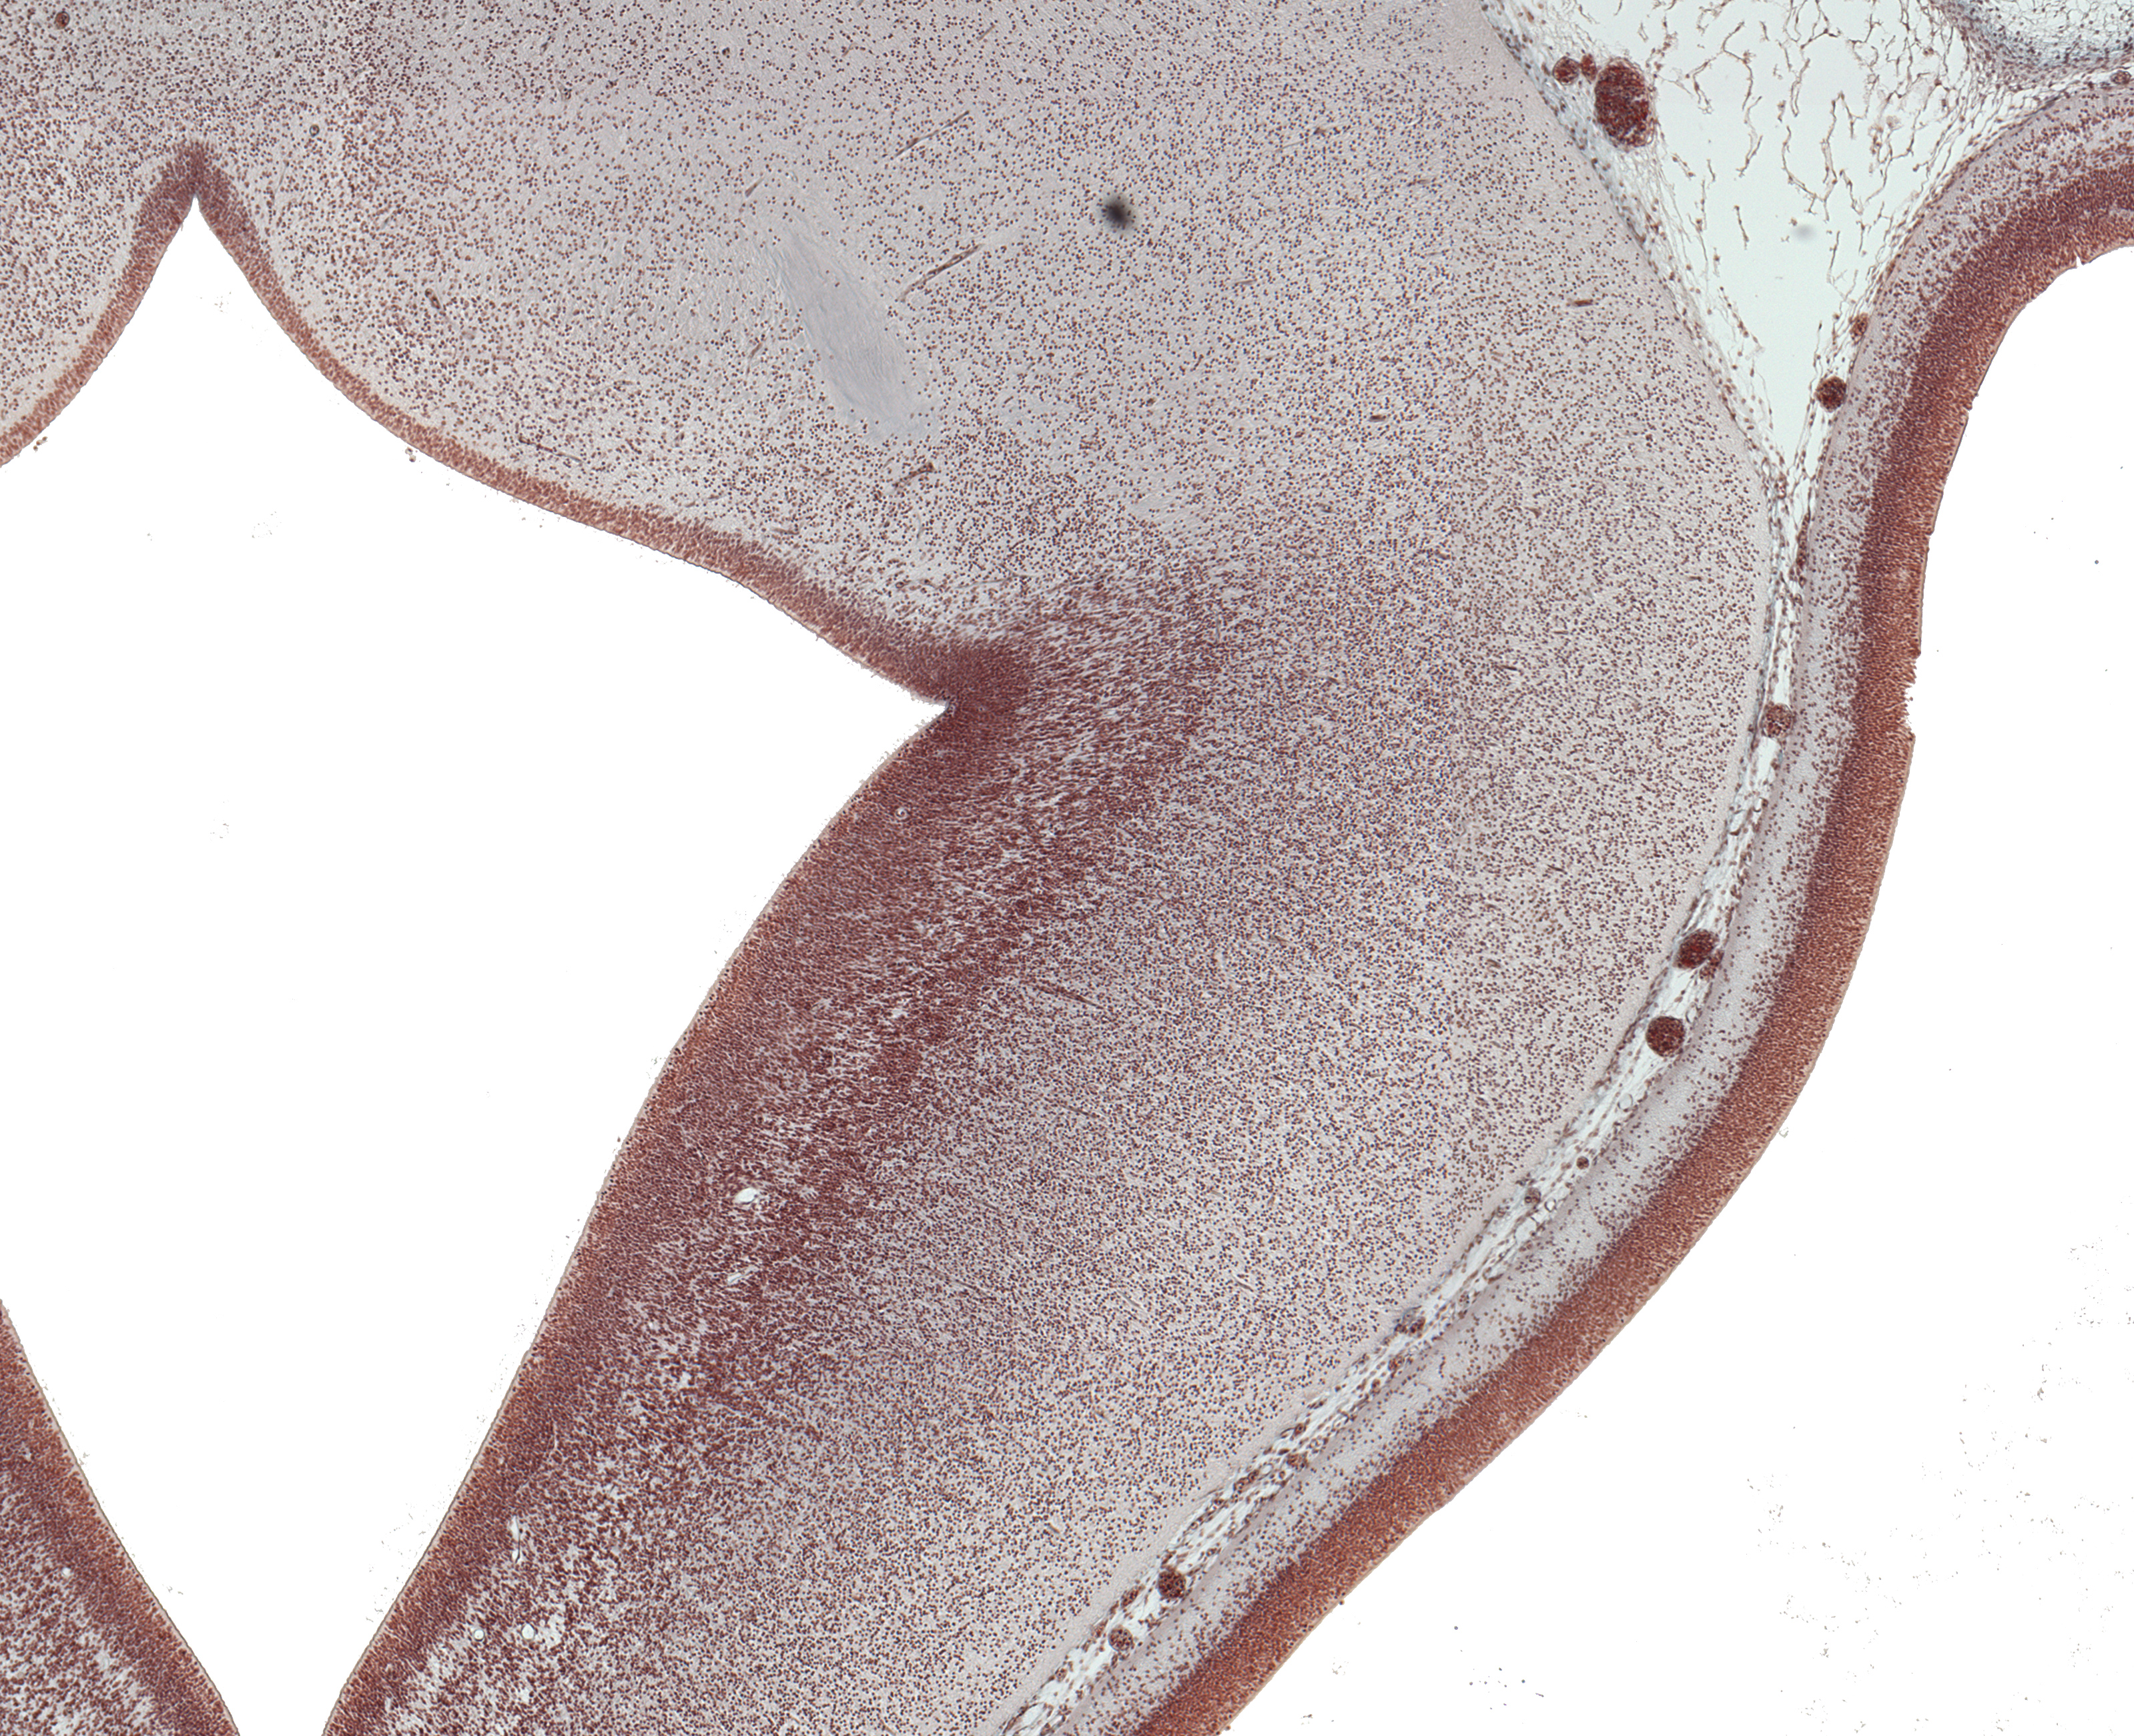

Tissue

–

Dorsal Thalamus and Basis Pedunculi

Carnegie Embryo #9226

Location:

26-01-01